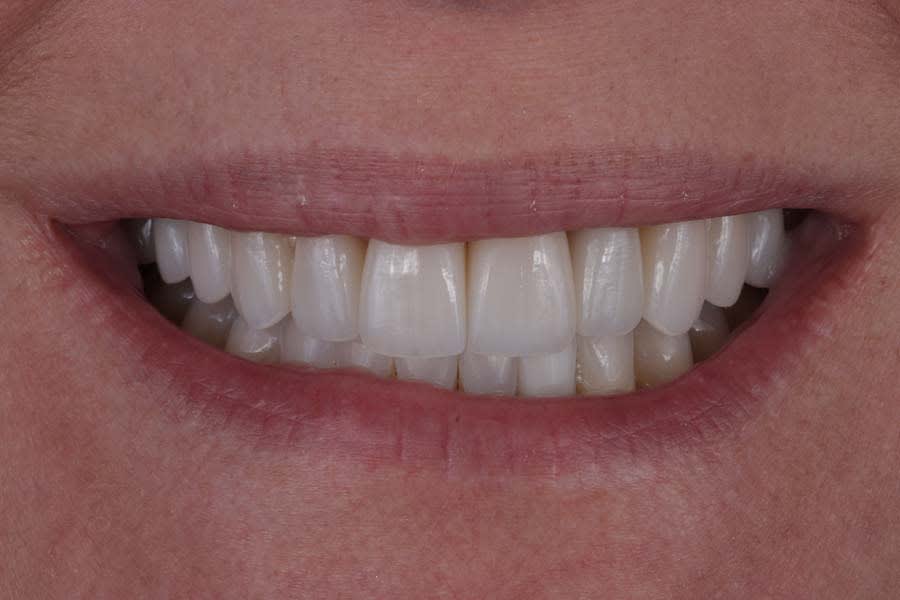

Post-treatment photographs demonstrating the successful outcome of the case are shown in Figure 15 through Figure 19.

This case exemplifies the transformative potential of a structured, systematic approach in transitioning a patient from single-tooth dentistry to comprehensive care. By addressing biomechanical, functional, periodontal, and dentofacial risks through integrated orthodontic and restorative treatments, the treatment achieved a stable, functional occlusion and an esthetically pleasing smile. The use of clear aligners, precise occlusal management, and cohesive restorations resolved immediate concerns and reduced long-term risks. Since treatment completion in early 2023, the stability of the restorations and the patient’s satisfaction have underscored the success of this approach in delivering lasting functional and esthetic outcomes.